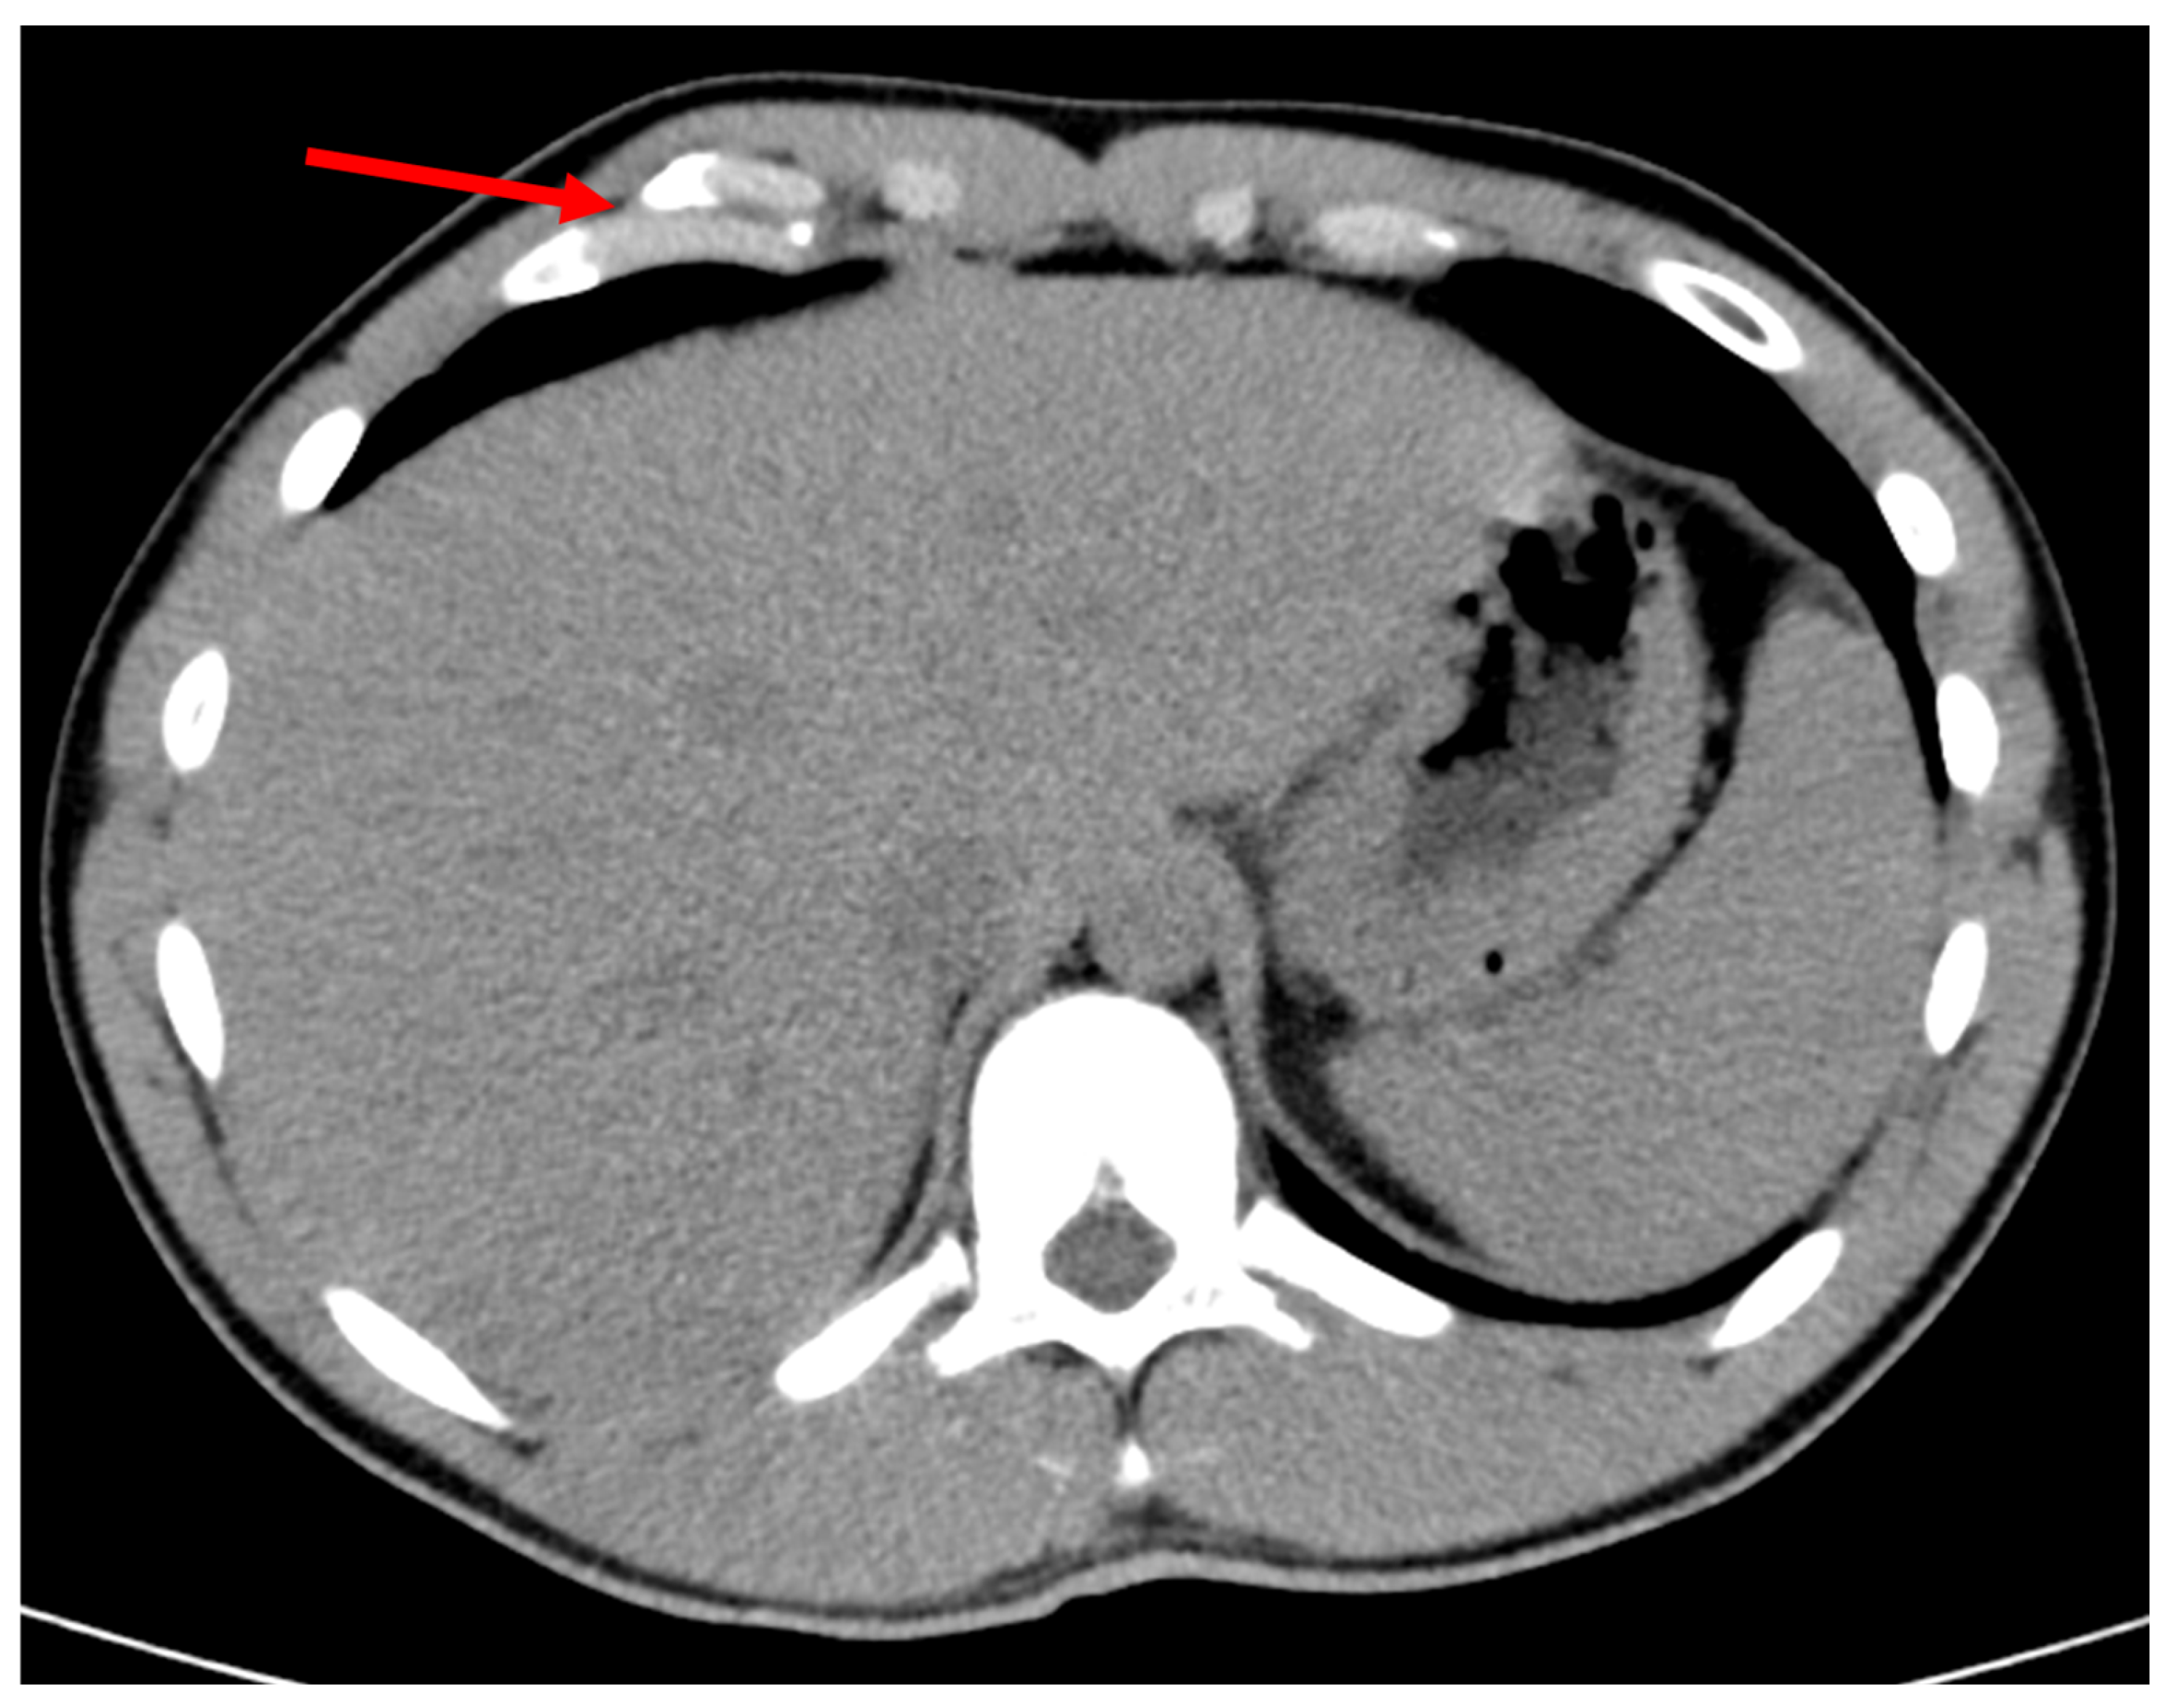

Figure 2.

Non-union fracture of the 6th costal cartilage. Red arrow points to the location of injury.